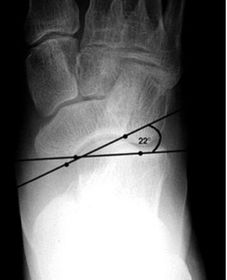

| What is this angle called? What is normal? What does an increased angle indicate? | Talo-calcaneal angle. 25-45 degrees. Increased angle = hindfoot valgus |